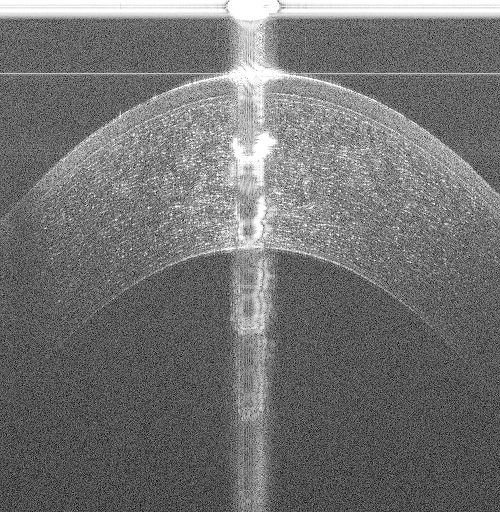

While many non-proprietary image analysis-based corneal interface segmentation approaches exist [6, 7, 8, 9, 10] in literature, they do not generalize to volumes acquired from different OCT scanners. These approaches are ad-hoc with key parameters being chosen manually; for example in Fig. 1, recent approaches [6, 7, 10], developed for images (B-scans) acquired by a Spectral Domain OCT (SD-OCT) scanner scanning a 66mm area, failed while segmenting the Epithelium (shallowest layer) in 33mm volumes acquired by a Ultra High Resolution OCT (UHR-OCT) scanner. Assumptions on the central artifact location [6, 7, 8, 9, 10] break down when they are located in different regions of the image (see Fig. 1(c)). As shown in Figs. 1(a) to 1(c), a segmentation approach must perform reliably across datasets acquired with different scan settings from different scanners, even in the presence of strong vertical and horizontal specular artifacts.

(a)

(b)

(c)

(d)

(e)